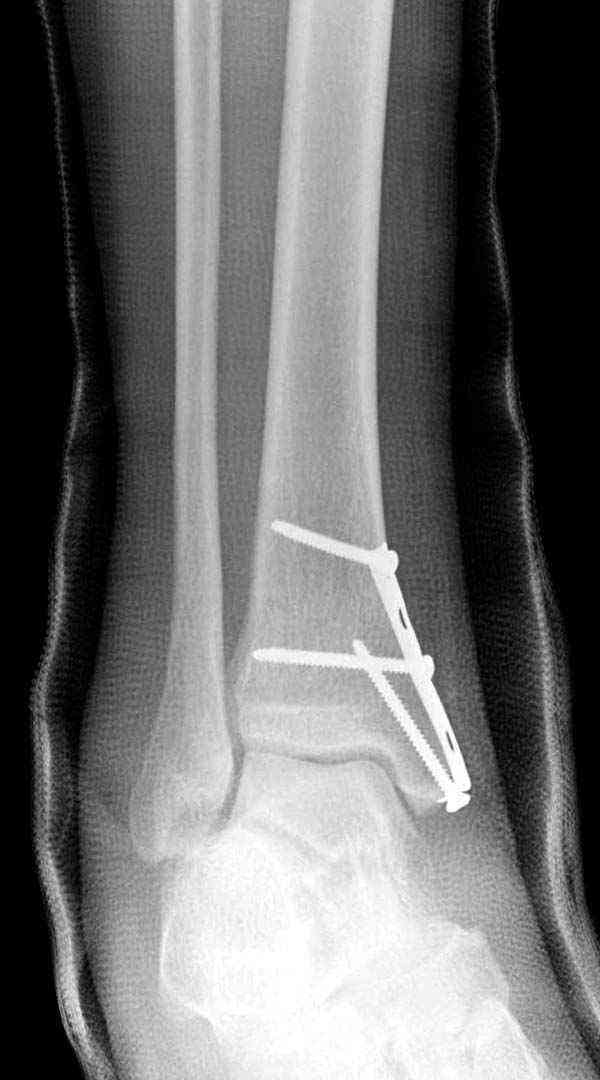

Случай прошлого года:пациентка-молодая ,крупная женщина ,30лет.Травма в начале апреля 2009г-пронационный перелом лодыжек с подвывихом стопы.Ко мне обратилась через 35 дней,прооперирована 22.05.2009г.Внутренняя лодыжка фиксирована по Веберу,наружная реконструктивной пластиной с наложением болта-стяжки.Иммобилизация "сапожок" в течении месяца,затем пригипсовано "стремя".Гипс снят 10.07.2009г

Достаточно быстрое восстановление функции.В октябре 2009г-почувствовала боль,в области рубца над гайкой открылся свищ.На Р-граммах-консолидация переломов и смещение гайки по стяжке.10.11.2009г-конструкции удалены,санация,заживление ран.В настоящее время пациентку ничего не беспокоит.На операции-раскручивание гайки-болталась на конце стяжки.Вопросы:какой механизм раскручивания и что я неправильно сделал?Свои версии:1)в области синдесмоза успела образоваться рубцовая ткань,которая при движении в суставе"пружинила",поскольку голеностопный сустав является спиральным, то и биомеханика подобна кривошипному механизму.2)Реконструктивная пластина не "реконструировалась" по форме лодыжки.Наложил,как есть.То есть подпружинивала сама пластина.Ну,это мои догадки.Что нужно,чтобы избегать впредь таких,пусть и не "страшных"осложнений:Рассверливать через лодыжку область синдесмоза?Ставить шайбу-гровер?Тщательно моделировать пластину?Прилагаю сравнительные снимки-сразу после операции и перед удалением конструкции.

Визуально никаких вопросов по репозиции не было.Да и на основании чего сомнения,что наружная лодыжка не полностью репонирована или прорезалась проволка ???Я не вижу...Снимок после репозиции справа.

Раз ,есть желание посмотреть другую проекцию выкладываю-ну лучшего качества нет...